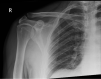

Inferior scapula avulsion fractures are rare injuries, with few cases reported and only a small number managed operatively discussed in the literature. We report the case of a man in his 40s who fell from a height and presented with right-sided scapular winging and point tenderness at the inferior pole of his right scapula with no neurological deficit. Radiographs and CT diagnosed avulsion fracture of the inferior scapula. The patient underwent surgical fixation and, following a course of physiotherapy, successfully recovered with no residual winging and full range of movement.